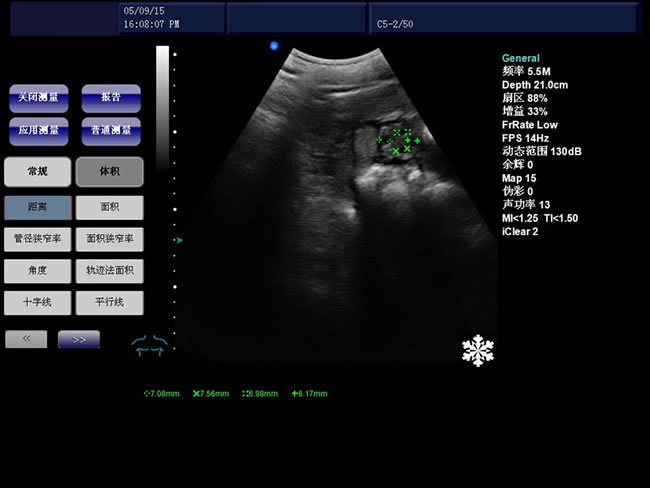

S9 彩色多普勒獸用超聲診斷儀

• S9彩色多普勒獸用超聲診斷儀是徐州市大為電子設備有限公司推出的一款全新的彩色超聲診斷儀器。

B模式基本測量:距離、角度、周長和面積(橢圓法、軌跡法)、體積、直方圖、斷面圖